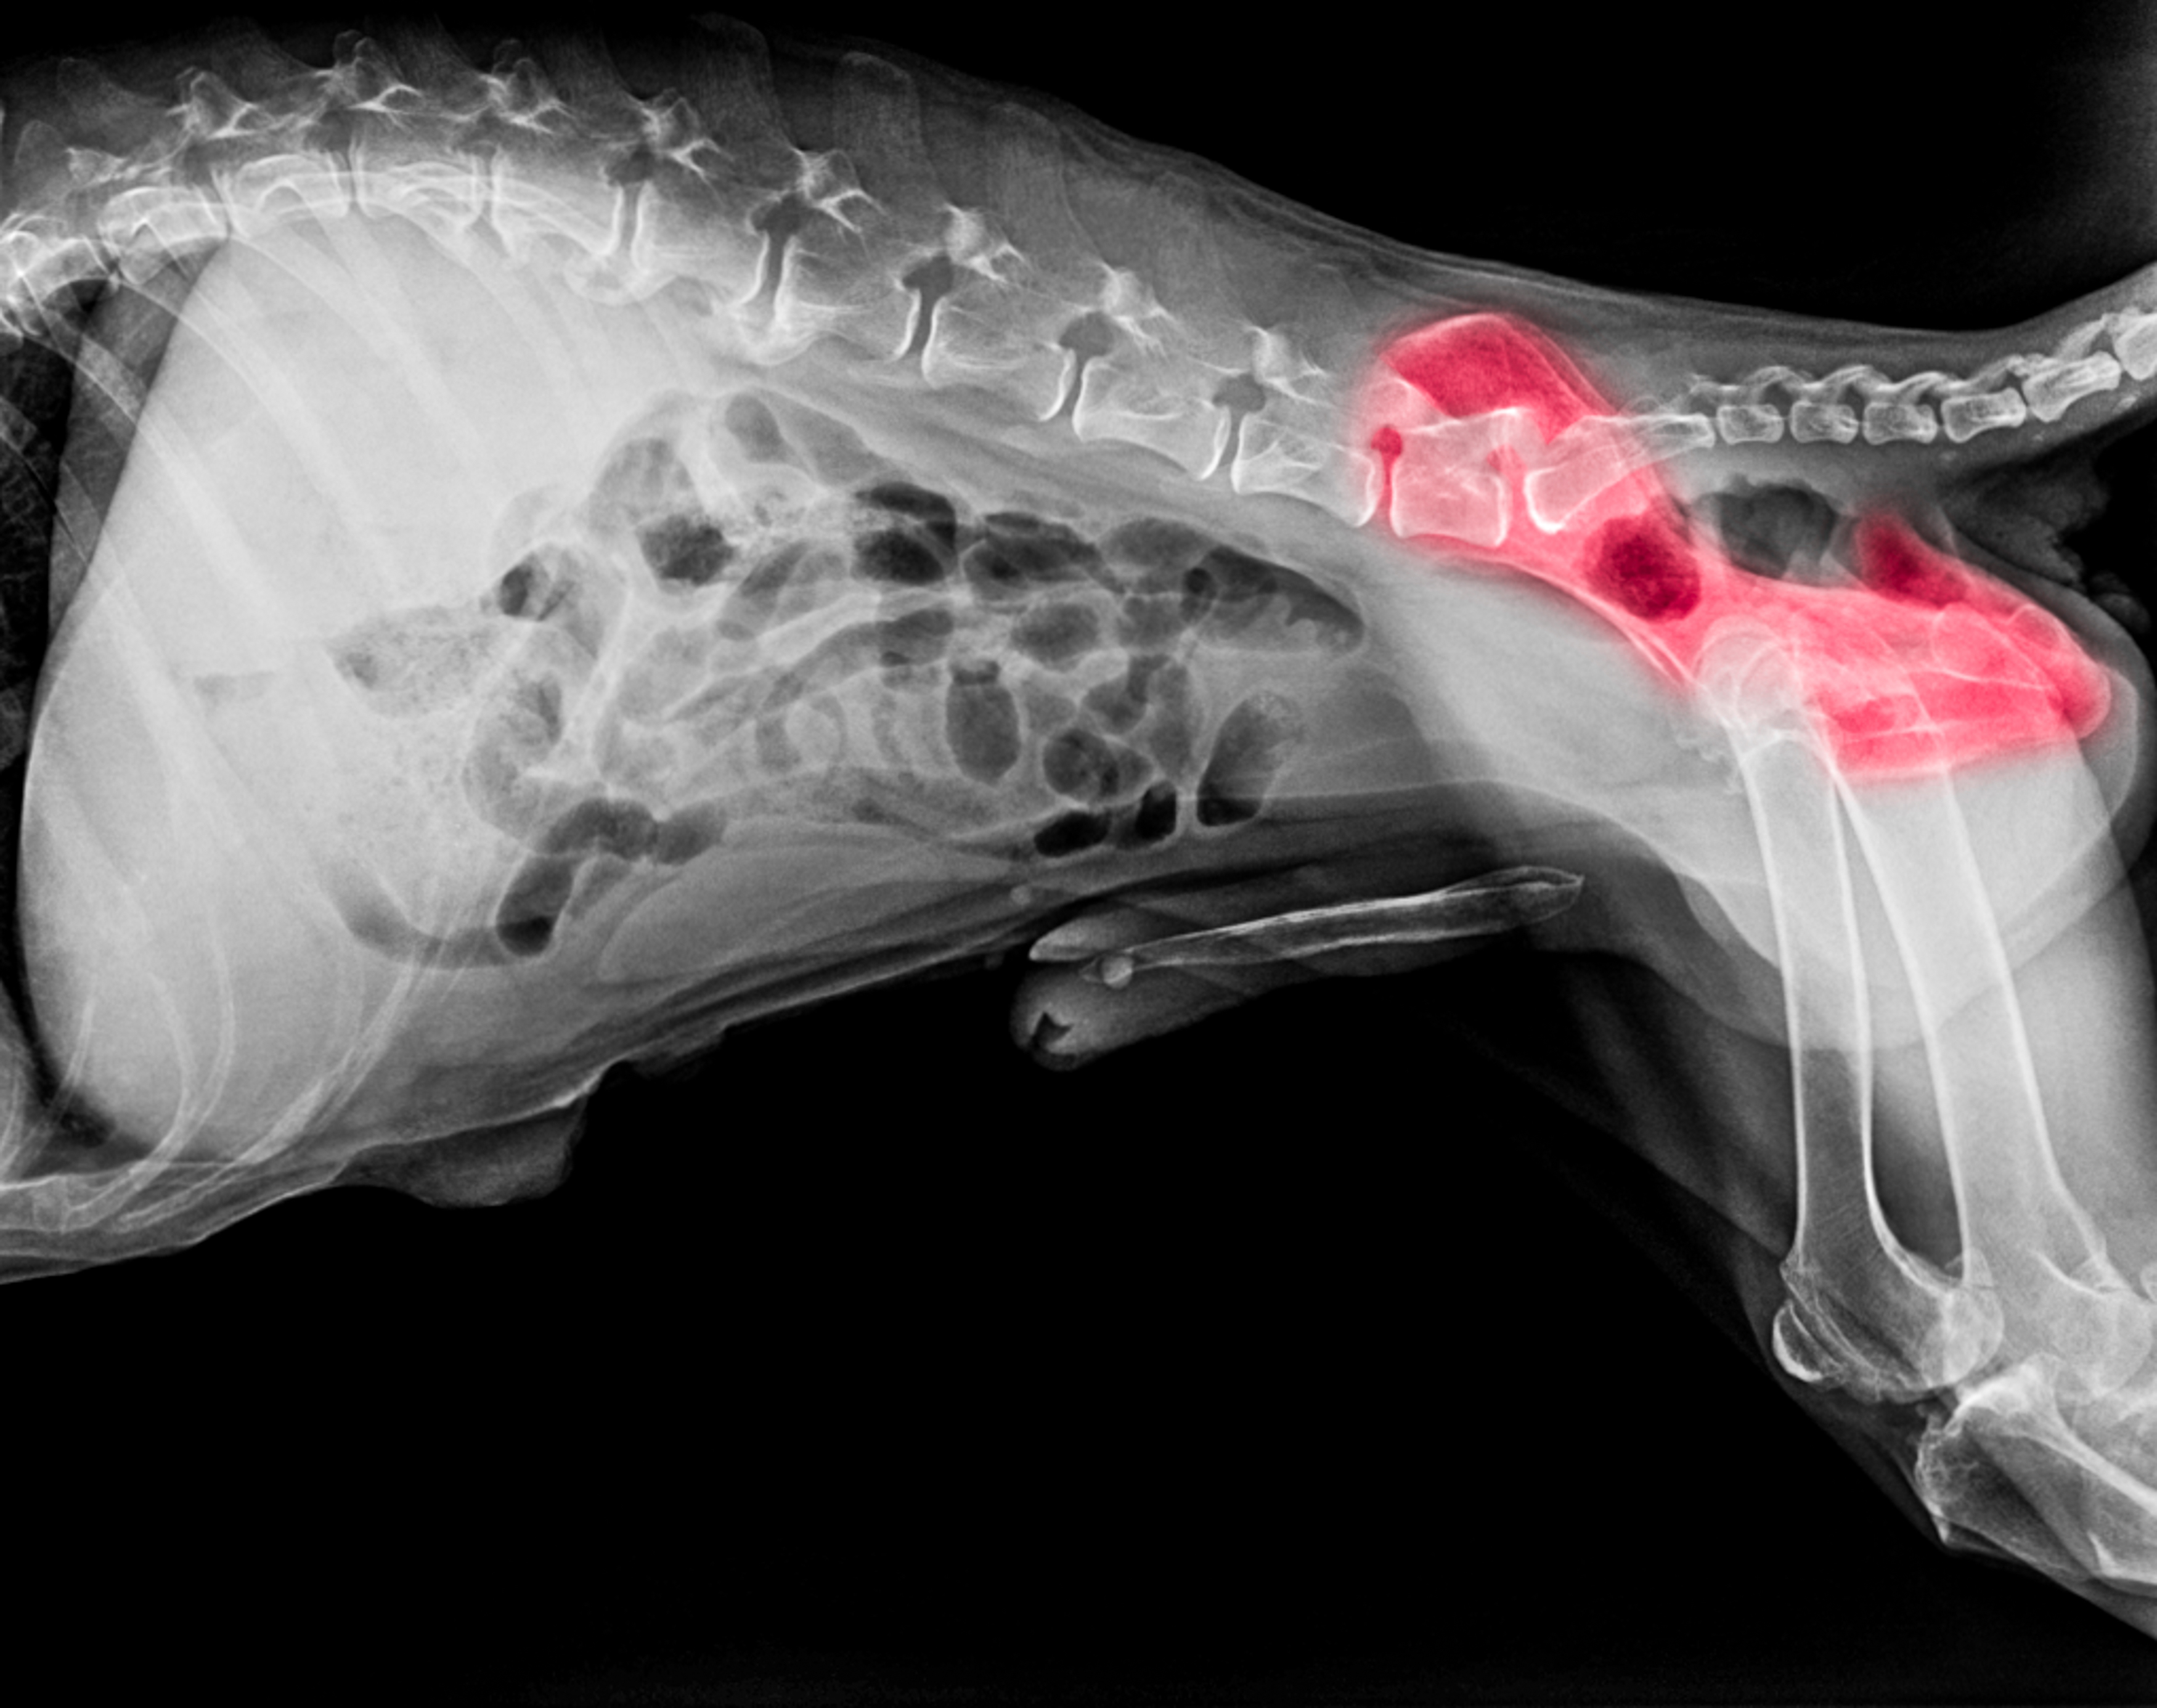

PennHIP is one screening method that measures the laxity of the hip joint using three different radiographic (x-ray) views or positions:

The distraction view and compression view are used to precisely measure:

The hip-extended view provides a supplementary assessment of the presence of osteoarthritis (OA) in the hip joint.

From assessment of the three images, dogs are given a distraction index (DI), which is a measurement of the laxity in the hip joint - the higher the number, the looser the hip joint. The individual dog’s DI can be compared to the overall breed average DI to aid breeders when making breeding decisions. Including dogs with a DI below the breed average in a breeding program helps shift the population in a lower-risk direction while still maintaining genetic diversity. DIs have shown a high level of heritability (although the figure varies between breeds).